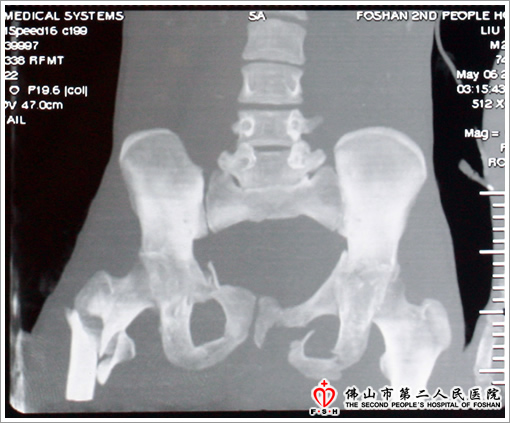

患者刘某,22岁,湖南人,因工作不慎身体被3000公斤铁板压伤15分钟左右入我院急诊科。当时患者处于休克抑制期,会阴部、右胸部的伤口虽经急诊科医生现场紧急加压包扎,但仍有活动性出血。我院立即开通绿色抢救通道,医务科组织骨科、泌尿科、肛肠科、胸外科、麻醉科等科室主任紧急会诊,紧急输血一万多毫升,并成立以骨科曹兴海主任、魏人前博士为主的救治小组,初步诊断为复合外伤:失血性休克、开放性骨盆骨折、开放性双侧髋臼骨折、右股骨粗隆间粉碎性骨折、右侧骶骨骨折、胸椎骨折、右锁骨开放性骨折,右侧骶髂关节分离、踝关节骨折脱位、肝包膜下破裂、会阴部撕裂伤,后尿道断裂、直肠破裂、马尾神经损伤。经过多科会诊后急诊入手术室行骨盆外固定支架固定及会阴部清创VSD闭式引流术+膀胱造瘘术,术后入ICU监护治疗。后期待患者病情稳定后行全身多处固定切开复位内固定及会阴部VSD多次更换缝合、肛门重建术。目前患者能在床上自由翻身活动,大便能够自行排出,全身各处骨折照片复查对位对线良好,并有骨痂生长。